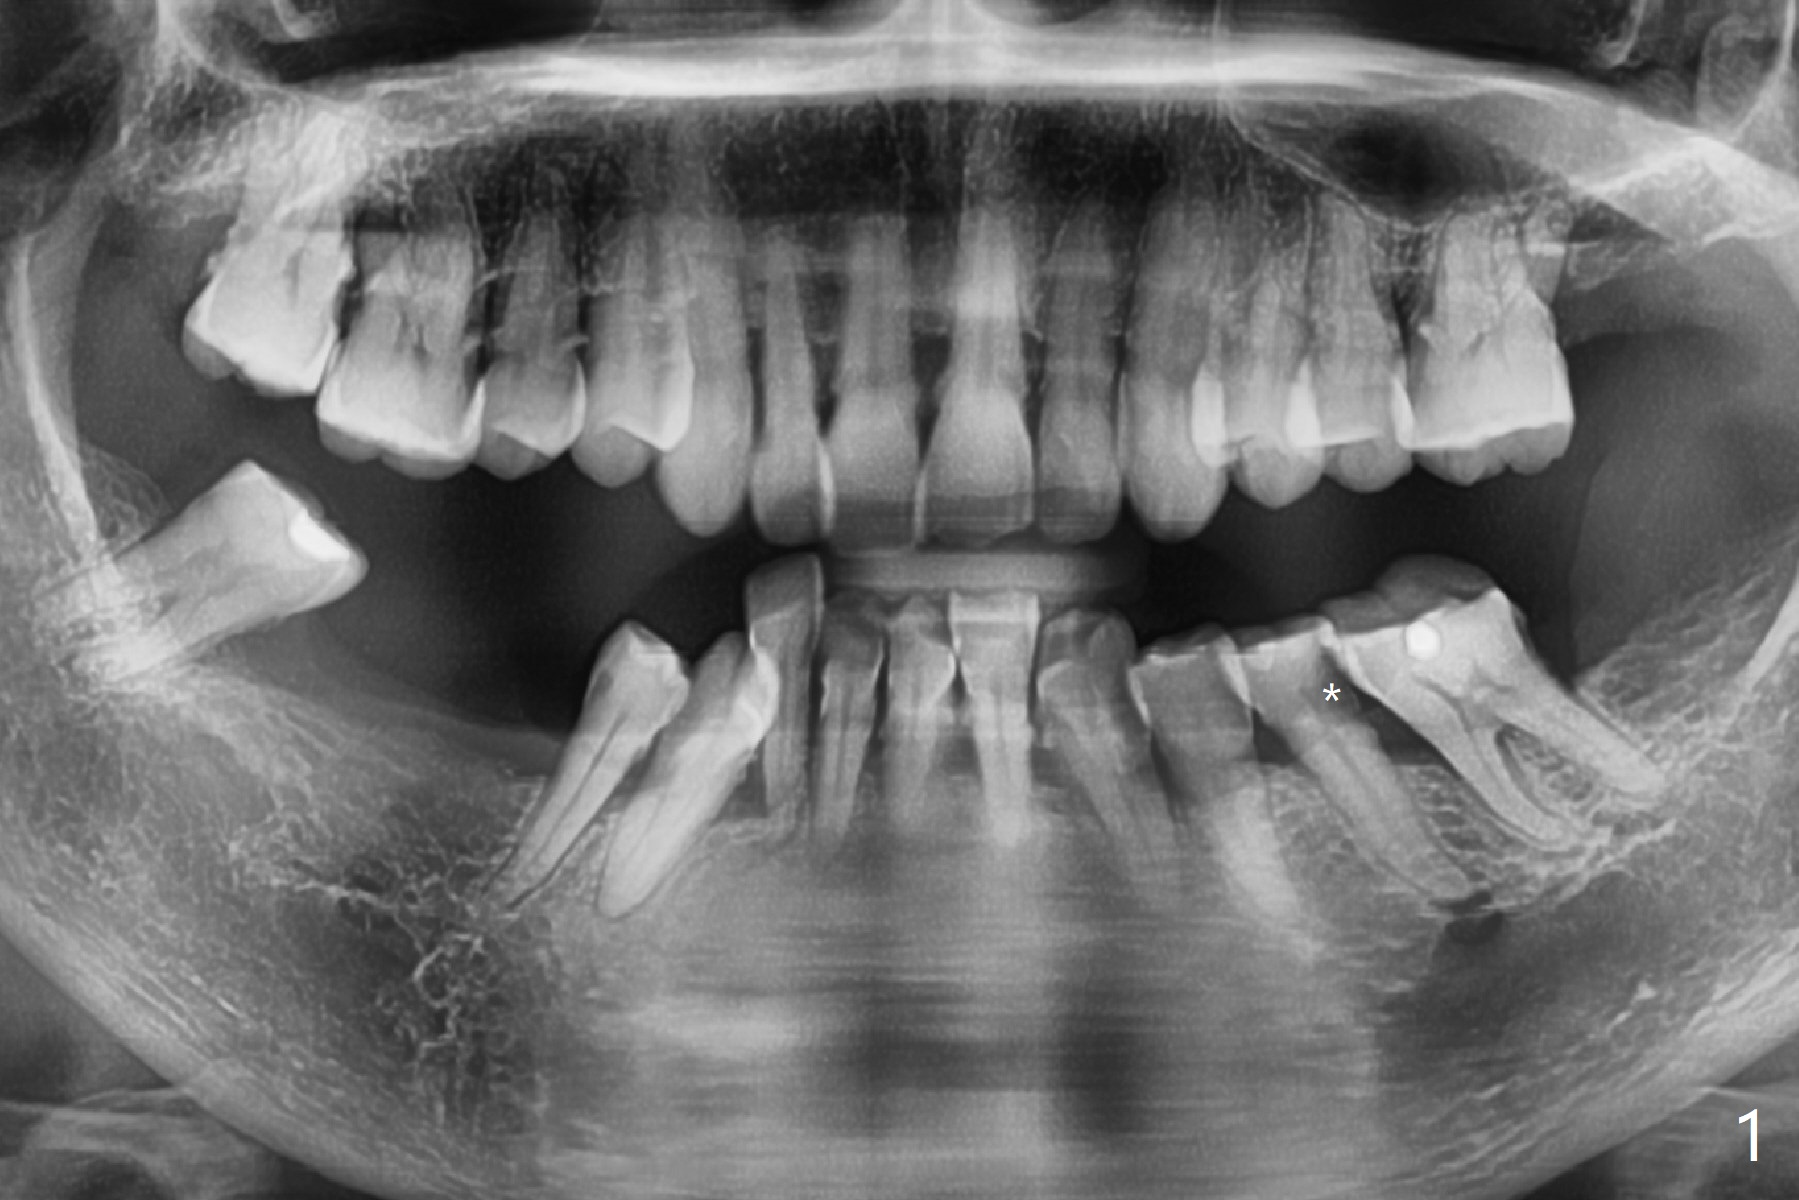

A 62-year-old woman chooses extraction and implant over RCT at #20 because of DO caries (Fig.1 *). After extraction, osteotomy will be initiated in the mesiolingual slope of the socket to reduce the chance of injury to the Mental Loop (Fig.2 red dashed line). Lower left SRP will be done at the same appointment. In fact the patient insists on extraction and socket preservation. The extraction turns out to be difficult because of tooth fracture and the curved root tip. The socket remains intact. Premolar socket opening is smaller than molar one. Socket preservation should be successful.